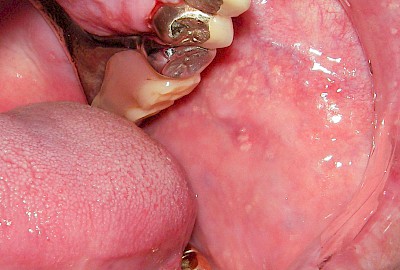

Talgdrüsen

Talgdrüsen sind wichtig für die Haut und machen diese widerstandsfähig gegen Reibungen aller Art. Die Schleimhaut jedoch braucht keine Talgdrüsen, da der Speichel die Oberfläche gut befeuchtet und damit gegen Reibung schützt. Trotzdem kommen – bei manchen Menschen durchaus sehr ausgeprägt – solche ektopen (außerörtlichen) Talgdrüsen vor. Diese haben keinen Krankheitswert und müssen nicht behandelt werden. Ektope Talgdrüsen zeigen sich häufig flächig verteilt und fallen vor allem auf im Bereich der Wangenschleimhaut oder der Lippen.